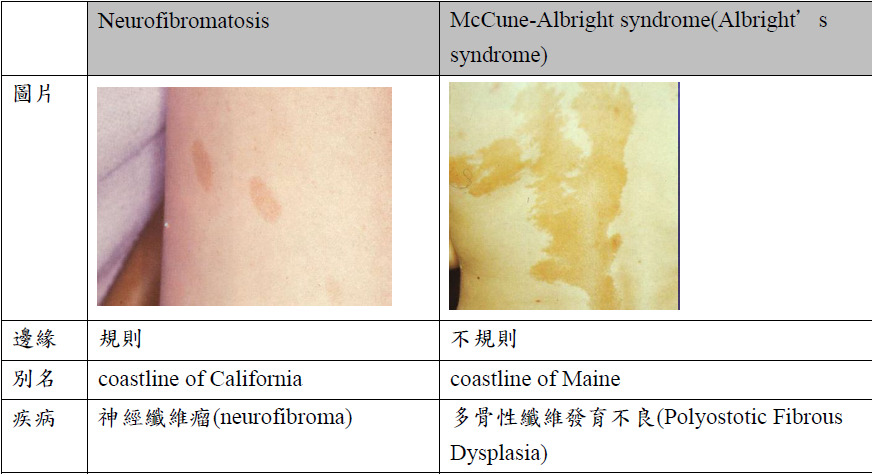

Neurofibromatosis

- cafe-au-lait spots disease (咖啡牛奶斑)

- neurofibroma (神經纖維瘤)

McCune-Albright syndrome (Albright’s syndrome)

- 咖啡牛奶斑

- 遺傳性疾病

- 多骨性纖維發育不良(Polyostotic Fibrous Dysplasia)

咖啡牛奶斑